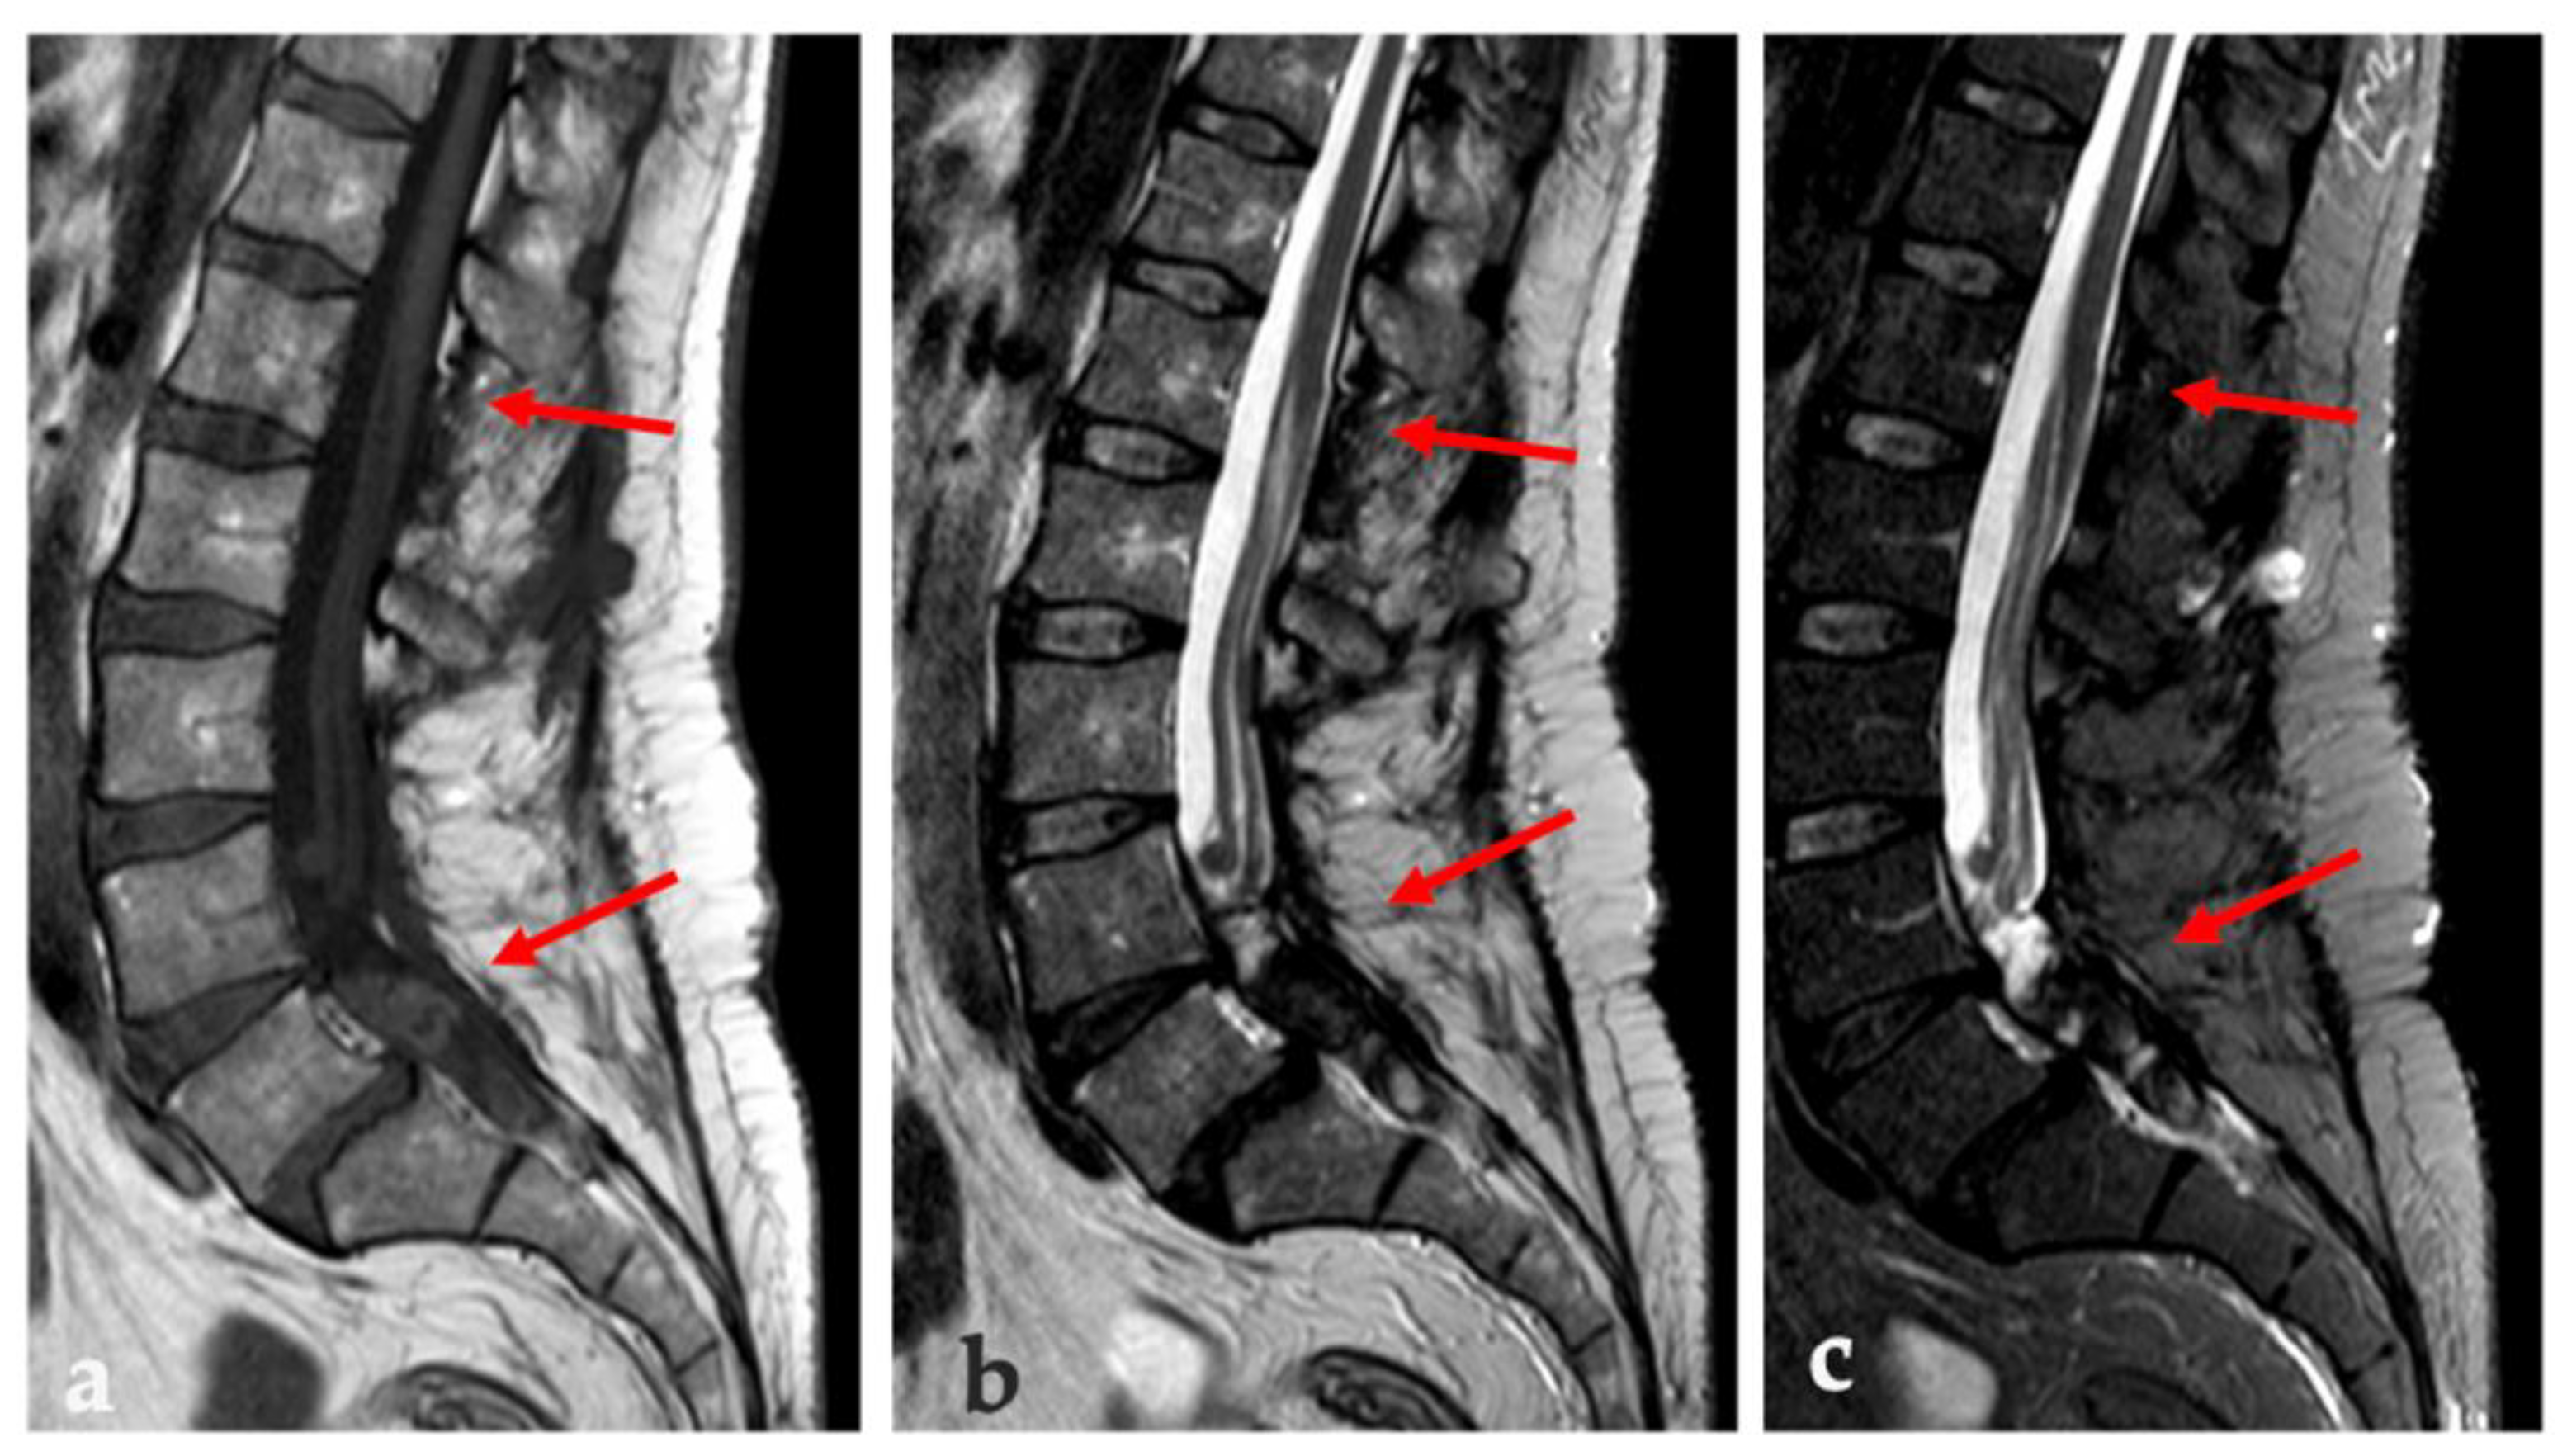

| MRI | Nonspecific: low SI on T1w; high SI on T2w; variable C.E. | Identical to fat; no C.E. | Adipose areas; non adipose areas: low SI on T1w, high SI on T2w, variable C.E. | Nonspecific: intermediate SI on both T1w and T2w | Low to intermediate SI on T1w; high SI on T2w; a small rim of fat and edema in adjacent muscles; variable C.E. |